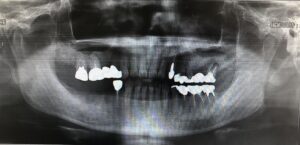

| 備考 | 右下6番の近心根と分岐部が歯根破折により腫れて痛みがあるとのことで来院されました。 抜歯と同時にインプラントを埋入する抜歯即時インプラントを行い、骨欠損部には骨補填材を填入しGBR(骨造成)を行いました。右下6番の治療中に右下7番の近心に虫歯があったため、銀歯を除去し、セラミックインレー修復を行いました。 見た目も綺麗になり、腫れることもなくなったため、患者様はとても満足されていました。 現在はエアフロークリーニングを行いながら経過をみています。 体調を崩した時、疲れた時などに腫れたり膿が出る歯がある方は一度ご相談ください。 |